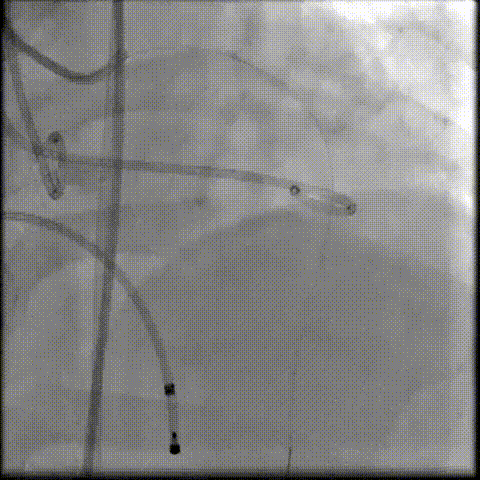

瓣膜工作位释放“烟囱支架”;

瓣膜(AV23)完全释放后,“烟囱支架”后扩

最终造影,“烟囱支架”显影清晰,瓣膜形态及LCA灌注良好

超声影像

TEE影像,烟囱支架显影清晰,支架内血流通畅